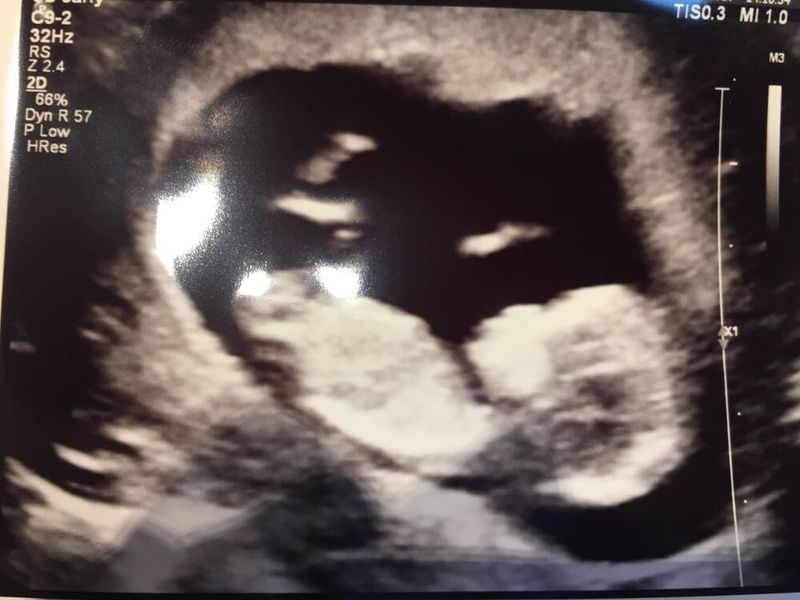

Er volgden maanden van wachten en onzekerheid. In december 2016 voelde ik me anders dan anders en werd ik niet ongesteld. Ik deed een test. Het was gewoon gelukt: ik was zwanger! We konden ons geluk niet op! We vertelden het de kinderen en die reageerden verdeeld. Ze vonden het vooral spannend dat alles weer ging veranderen. Wij vonden dat ook! Ik lag er ‘s nachts weleens wakker van, want wat deden we onzelf en de kinderen eigenlijk aan? Tegelijk ging het idee ook steeds meer leven bij iedereen van het gezin en verheugden we ons uiteindelijk allemaal op de komst van dit kleine wonder. Ik leefde inmiddels in een droom. Zwanger zijn was zo heerlijk en zoveel intenser dan de eerste keer. We beleefden alles echt samen.